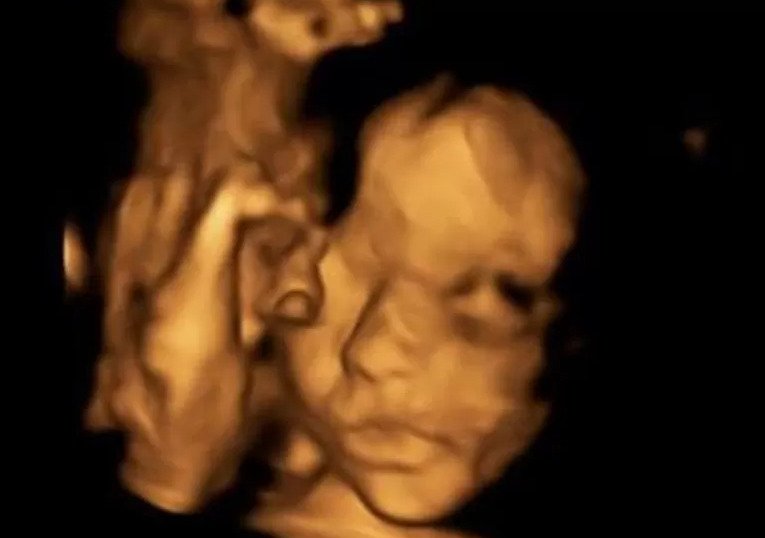

Όταν διαπιστώθηκε ότι το αγέννητο κοριτσάκι μόλις 20 εβδομάδων έπασχε από μία γενετική ανωμαλία, που ονομάζεται spina bifida (δισχιδής ράχη), οι χειρουργοί επενέβησαν και πραγματοποίησαν μία άκρως επιτυχημένη αλλά ριψοκίνδυνη επέμβαση

Έβγαλαν από τη μήτρα της μητέρας το παιδί της για να το θεραπεύσουν και στη συνέχεια το επανατοποθέτησαν πίσω για να ολοκληρωθεί η κύηση.

Το αγέννητο κοριτσάκι ήταν μόλις 20 εβδομάδων, όταν το υπερηχογράφημα Β΄ επιπέδου της Μπέθαν Σίμπσον από το Έσσεξ εντόπισε ένα πρόβλημα που είχε στη σπονδυλική του στήλη.

Η ασθένεια από την οποία έπασχε το μωρό επηρεάζει τον νωτιαίο μυελό και εμπόδιζε τη σωστή ανάπτυξή του.